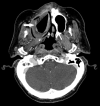

Axial postcontrast CT images demonstrate 2 other examples of patients status post maxillectomy for tumor resection, with Trusoft obturators (arrows) containing trapped internal foci of air.